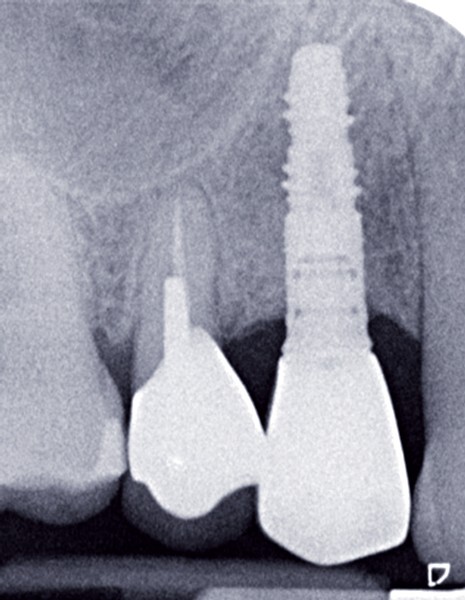

Le contrôle radiologique rétro-alvéolaire montre, quant à lui, une parfaite préservation de l’ostéointégration à 6 ans(fig. 3a et b).

Cette ostéointégration est confirmée par le Cone Beam(fig. 4a et b).